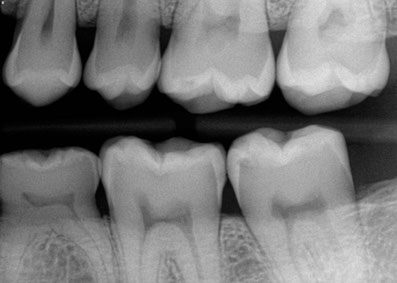

• Diagnostic X-rays